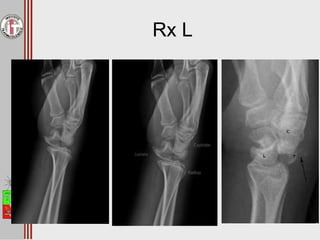

Rx L

• #27 En la Rx lateral ya se ve con mayor evidencia la luxación carpiana con perdida de la congruencia entre el semilunar y el hueso grande. En la imagen de más a la derecha se puede ver que el semilunar se mantiene en su lugar pero hay una completa luxación del grande que esta por dorsal y una fractura del piramidal tambien desplazado hacia dorsal Fuera de la Rx se podrían pedir otros estudios como el TAC, pero la verdad es que en agudo no es necesario puesto que lo que se busca es la reducción de la articualcion. Si pueden ser utiles para la evaluación prequirúrgica sobre todo si hay una fractura u otras lesiones asociadas